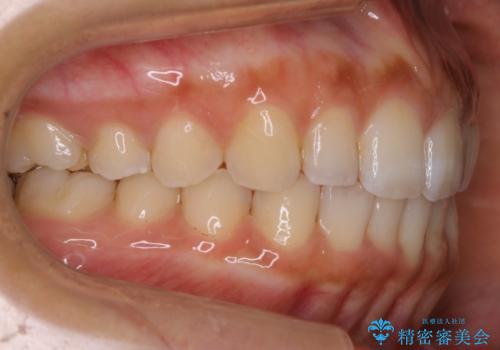

奥歯の噛み合わせに問題がなく、矯正で必要となる歯牙の移動量が軽微である場合に部分矯正が適用になる場合があります。

変える必要のない部分には手を出さず、必要な部分に最小限の処置を施すことで費用や期間の削減をすることが可能となります。